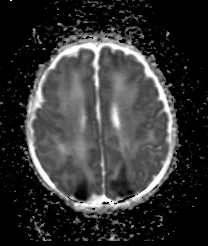

MRI Scan

MRI map of water diffusion shows bilateral posterior brain injury (dark areas) in a 5 day old baby.